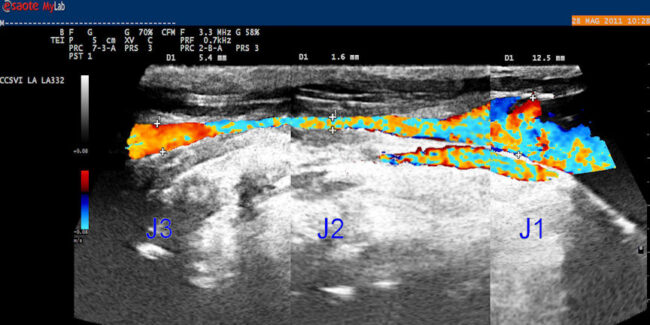

Le malformazioni venose del collo alla base della CCSVI. Come descritto in un altro articolo la CCSVI, o insufficienza venosa cronica cerebrospinale, è una condizione caratterizzata dalla presenza nel collo di vasi venosi malformati. Le malformazioni interessano prevalentemente le vene giugulari, che scaricano gran parte del sangue di ritorno al cuore dai settori cerebrali. In…